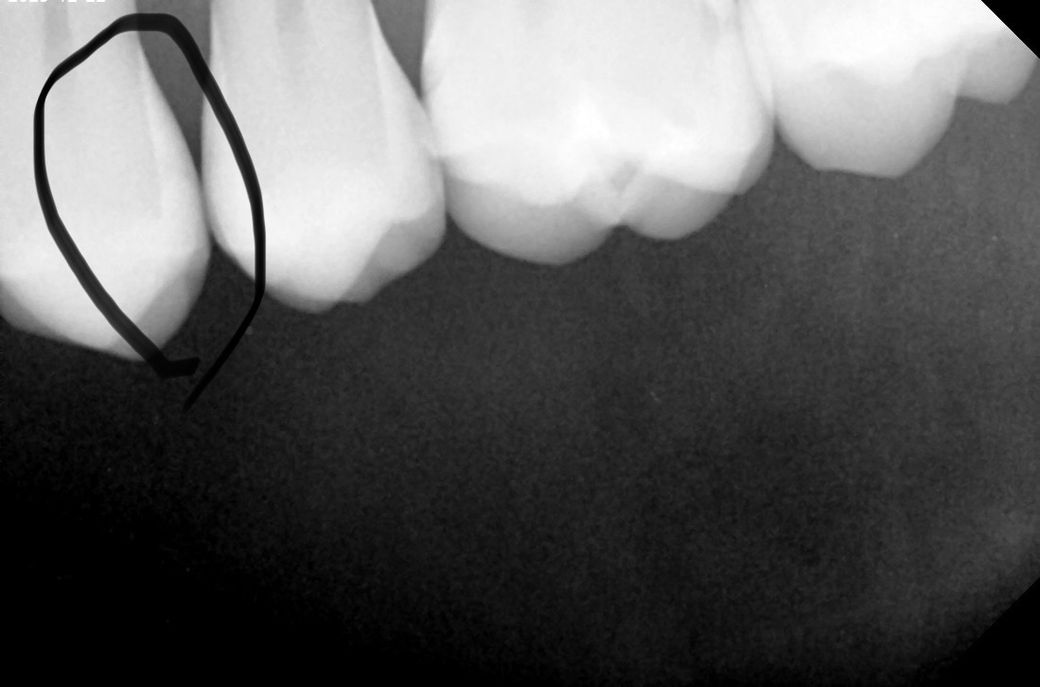

인접면 충치를 잘 잡는다는 교익 촬영까지 했습니다

• 3번 째 사진

교익방사선 촬영을 통해서 해당 부위의 미세한 충치가 있기는 합니다. 하지만 이 부위를 치료하기 위해서는 더 큰 치질을 손상시켜야 하므로 치간칫솔이나 치실을 사용하면서 해당 부분을 관찰하는 것이 좋을 수 있습니다. 지금의 충치 정도로는 큰 불편감이 나타날 가능성은 적습니다. 아마 심리적인 요인일 가능성이 커 보입니다.

1. 사진 좌우 반전되거나 수정한게 아니라면 임상사진은 15,14번이고, 방사선 사진은 24,25 입니다

2. 14,15는 명백히 충치 있어보입니다